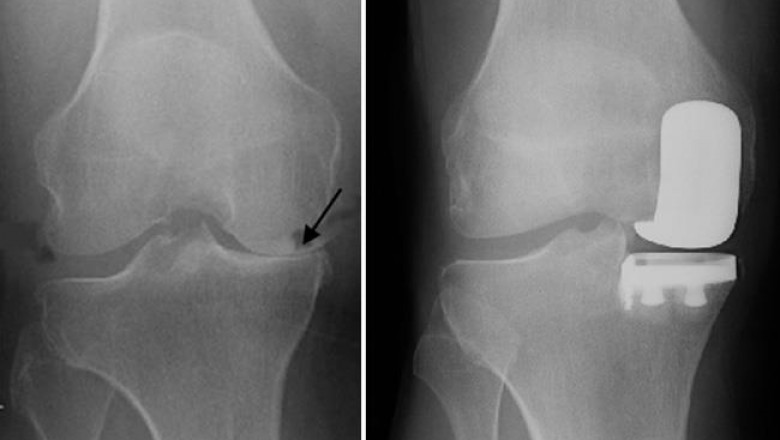

A partial knee replacement is a treatment advised by the joint specialist after analysing the situation of the knee, your arthritis, and the damage. The foremost step includes conducting an x-ray of the knee site to know about the damage condition. If your damage is more at one compartment, you are an ideal candidate for the treatment. In other words, only a portion of the knee is resurfaced. Therefore, it is called an alternative to total knee replacement.

The treatment procedure is not as complex as a total knee replacement has. During this treatment, the damaged compartment is replaced with a prosthetic that is made from metal or plastic. The surgery hours are not as long as for a total knee replacement. The aim of the surgery is to preserve the healthy cartilage and bone as well as the ligaments.